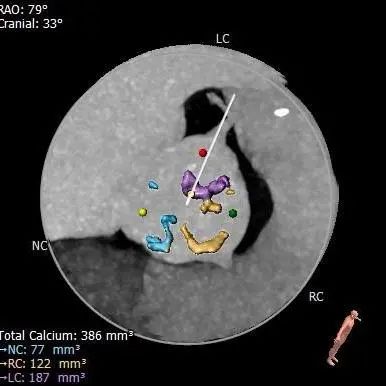

主动脉根部评估

CT 数据显示该患者为Type1型二叶式主动脉瓣

主动脉瓣瓣环周长72.5mm,周长径23.1mm

LVOT 周长 85.1mm,周长径27.1mm

SOV:31.1mm*33.6mm*31.6mm

STJ 周长 91.9mm

无冠瓣钙化严重,HU850:448mm³

瓣环水平夹角46度